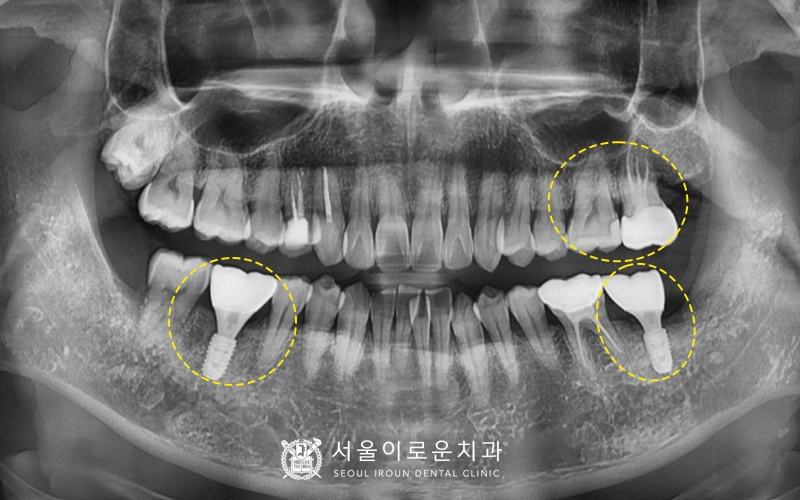

치아를 뽑고 발치와의 잇몸뼈가 아문 뒤에

왼쪽 아래 두번째 큰 어금니 자리에

뼈이식을 동반한 임플란트를

식립하였습니다 😀

앞서 말씀 드린바와 같이,

임플란트와 뼈가 붙는데 기다리는

약 3개월 정도의 기다리는 기간이

필요한데요.

이때, 다른부위에 필요한

추가적인 치료를 병행하기로 하였습니다~!

충치가 심해 통증이 있었던

왼쪽 위 두번째 큰 어금니는

(노란색 동그라미)

신경치료 후 크라운을 진행하였고,

바로 앞에 위치해 맞닿아 있는 면에

충치가 생긴

왼쪽 위 첫번째 큰 어금니 원심면에

인레이를 진행하였습니다 🙂

2달반 후

임플란트 픽스처와 잇몸뼈가

잘 붙었는지 확인하기 위해

마찬가지로

osstell beacon 장비를 활용하여

isq 측정한 뒤

안정값을 확인 후 보철과정을 진행하였습니다.